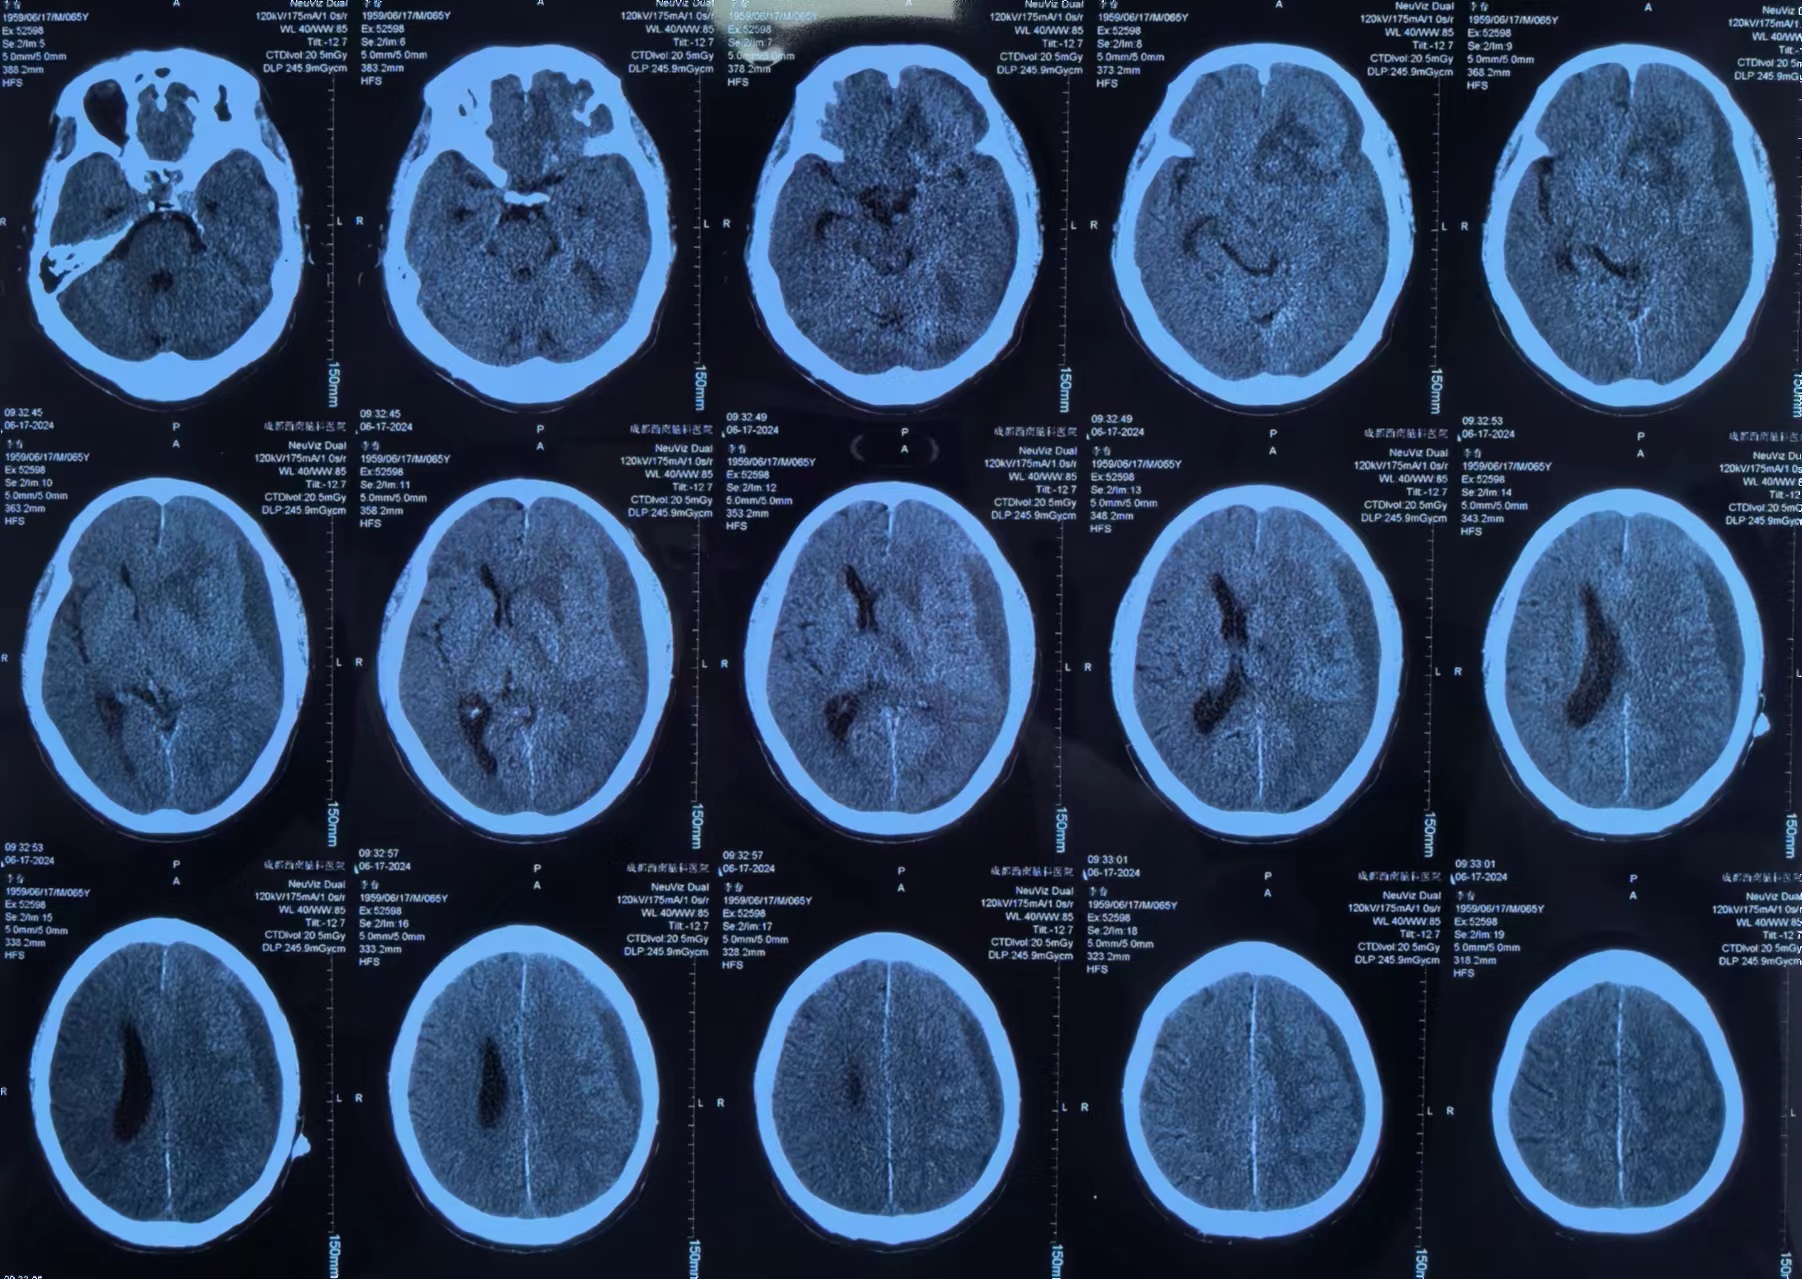

李先生有高血压病史3+年,最高血压166/88mmHg,血压控制一般。10+天前突然出现意识丧失,立即就诊当地医院。李先生送医途中就恢复了意识,但全头部爆炸样胀痛,诊断为脑出血、硬膜下血肿、蛛网膜下腔出血,大脑前动脉中度狭窄,颈内及大脑中动脉均发现动脉瘤。

因当地医院对症治疗一周效果不佳,为求进一步治疗,家人带着李先生辗转来到我院。经左剑主任与李积荣主任联合会诊,认为李先生目前的头痛主要与脑内血肿引起的脑水肿及硬膜下血肿引起的颅高压有关。因患者有多发颅内动脉瘤,最终决定局麻下采用“颅内血肿微创清除技术”清除硬膜下血肿。

颅内血肿微创清除技术是目前治疗高血压性脑出血最简单、最安全、最有效的方法。利用颅脑CT片或CT下进行三维立体定位,采用一次性使用颅内血肿微创穿刺针进行穿刺抽吸,外径只有3毫米,针钻一体,设计合理,操作简便,易固定,密闭性好,创伤小,不易感染,抽吸无盲区,相比开颅手术费用低廉,可以快速清除颅内血肿,缓解颅内压力,大大地降低了患者的死残率,提高了患者的生存质量。

术后李先生自觉头痛明显减轻,术后第三天复查头颅CT提示:硬膜下血肿基本清除,脑移位恢复正常。